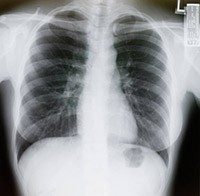

What to know about lung cancer screening, treatment and research

Lung cancer is the leading cause of cancer deaths, but new advances in prevention, lung cancer screening and research are helping to save more lives. And, here at MD Anderson, we're leading the fight against lung cancer by focusing on prevention, lung cancer screening and personalized lung cancer treatment through our Moon Shots Program, an ambitious program to reduce cancer deaths for several cancers and ultimately find cures for these...